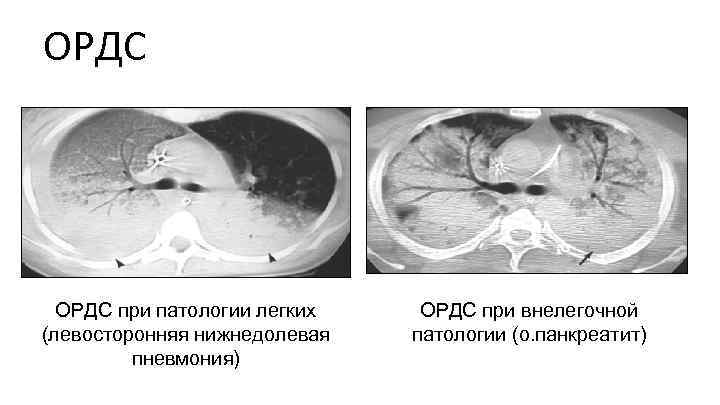

ОРДС Легочные причины: Внелегочные причины: • Поражение менее 80% легочной паренхимы • Поражение более 80% легочной паренхимы • Равное соотношение альвеолярной и интерстициальной инфильтрации • Преобладание интерстициальной инфильтрации (матовое стекло) • Часто ассиметричный характер альвеолярных изменений • Равномерное распределение уплотнений по типу матового стекла • Симметричное поражение Goodman L. R. et al. , 1999

ОРДС при патологии легких (левосторонняя нижнедолевая пневмония) ОРДС при внелегочной патологии (о. панкреатит)